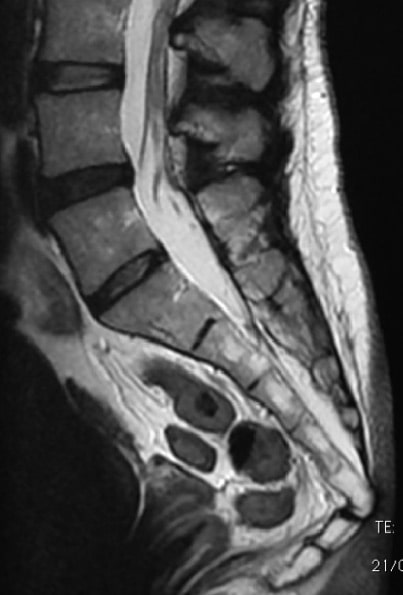

이 부위 탈구는 영상 자료로 비교적 덜 진단되는 탈구 중 하나입니다. 타 원인으로 척추 전체 또는 심지어 요-천추까지 MRI나 X-ray가 촬영되더라도 S2 밑으로, 미골까지 보이진 않기 때문입니다. 미골 끝까지 촬영 되는 경우라도 X-ray로는 그 분리가 잘 확인되지 않아 CT나 MRI 촬영이 요해집니다.